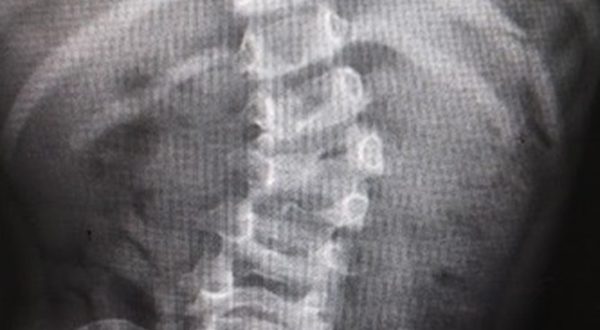

· La paciente tenía su columna en forma de “S”, hombros y caderas desnivelados y la deformidad podía comprometer órganos vitales como pulmones o corazón

La pequeña Fátima tenía dificultades para desplazarse y mantener una buena postura, ya que su columna vertebral tenía forma de “S”, y sus hombros y caderas estaban desnivelados, pero al cabo de los meses y por la exitosa cirugía, a cargo del equipo multidisciplinario del IMSS, ahora es capaz de correr.

Dijo que el caso de Fátima fue peculiar, ya que a su corta edad ella presentó una escoliosis de tipo congénito, lo que quiere decir que una de sus vertebras no se desarrolló correctamente y esto ocasiona que un lado no crezca de manera equitativa.